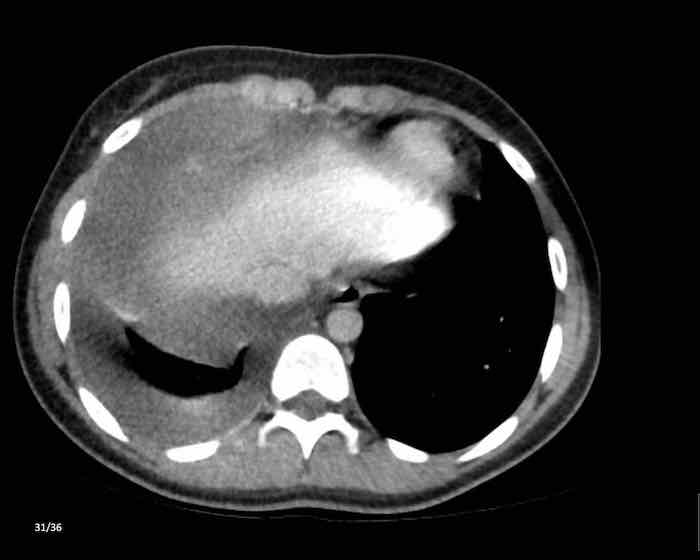

Các hình ảnh này của một phụ nữ 65 tuổi có tiền sử mắc bệnh Graves, một rối loạn tự miễn liên quan đến tình trạng cường chức năng tuyến giáp.

CT được thực hiện vì lý do ho ra máu.

Hình ảnh

Có một tuyến ức to lớn, cồng kềnh chứa mô mỡ đại thể.

Đây là hình ảnh điển hình của tăng sản tuyến ức.

Tăng sản tuyến ức trong bệnh Graves có liên quan đến tình trạng dư thừa hormone tuyến giáp và kháng thể kháng thụ thể thyrotropin.

Tình trạng này thường cải thiện sau khi điều trị thành công bệnh Graves.